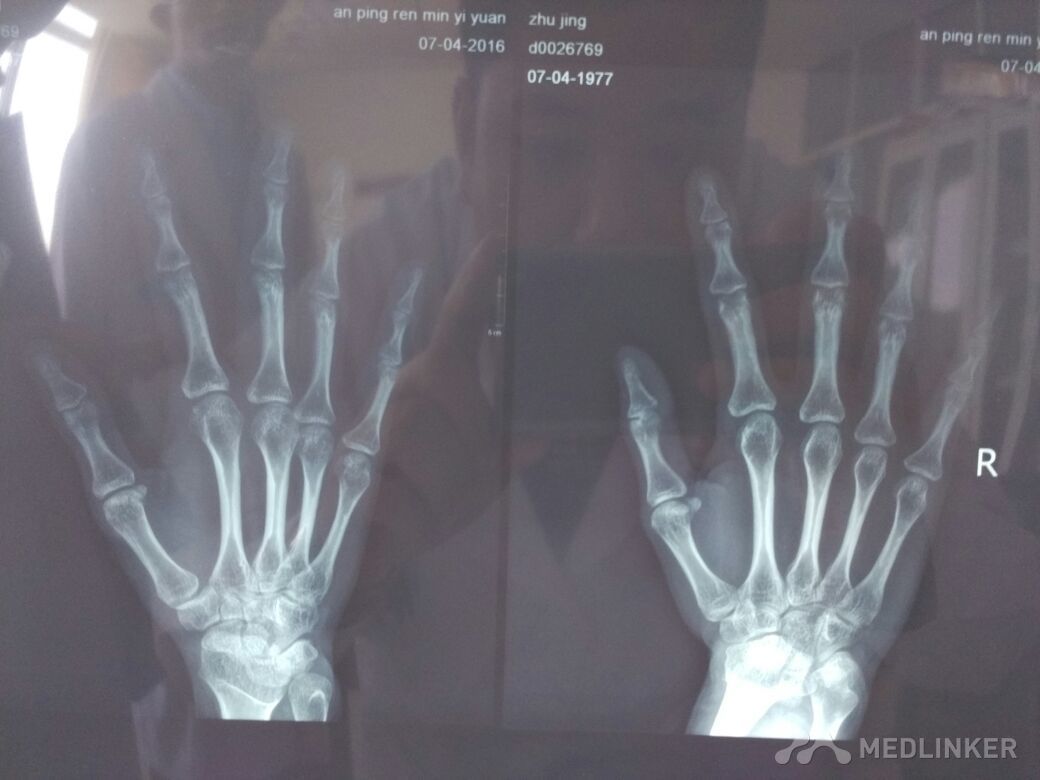

患者女性,40岁,右示指近指间关节疼痛1月余。?

X线提示:骨皮质增厚。各位老师同仁帮忙看看,如何诊治?